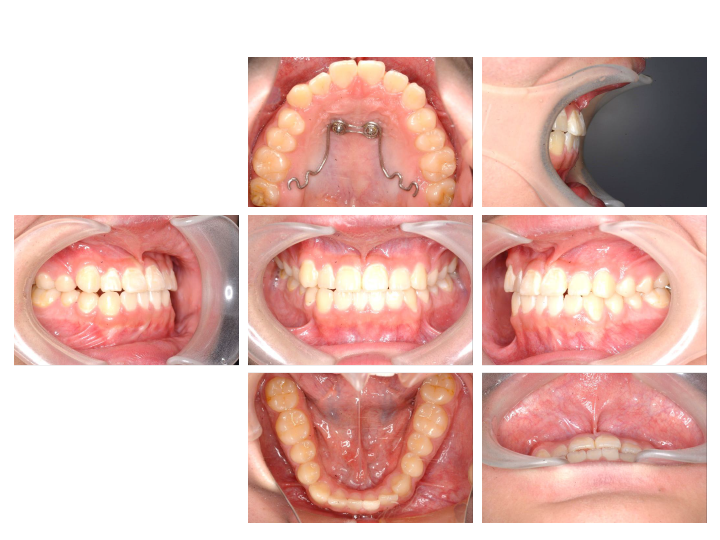

1.治療期間が短く7割が幼少期で完治

せっかく並べた歯が後戻りしないよう骨格から整え、短い期間で治療が終えられるようにサポートいたします。

2.治療完了までの費用が安い

通常10年かかるところを2年で終えられるため、治療開始から終了までのトータルで見ると費用を抑えて矯正ができます。

3.お顔が綺麗になる

口腔周囲筋にもアプローチし、お顔の骨格自体を整えることができるため顔貌も変わります。

骨格にアプローチする矯正治療で無闇に歯を抜いたりせず、自然と正しい位置に歯が並ぶよう、一人一人に合わせた確実な治療を行います。

5.違和感・痛みが少ない

骨の成長を利用して治療するため、成人矯正のように歯を動かしていく治療よりも痛みが原因で治療をやめてしまうことがありません。